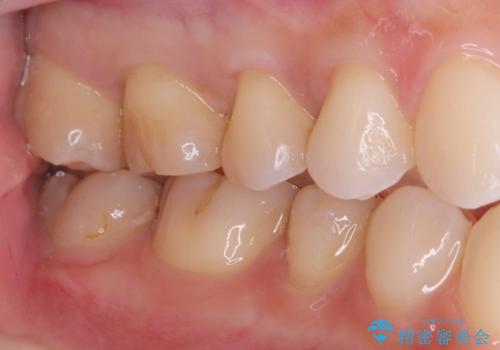

【セラミックインレー】咬合面のカリエス

- メンテナンス時に見つかった虫歯です。二次カリエスのリスクを下げる為に虫歯を除去後セラミックインレーで治療を行いました。

咬合面の溝が深く虫歯のリスクが大きい患者様です。

他の歯も咬合面に同じように虫歯ができて大きくなってしまった経験があることから今回は大きくそして深く進行する前に虫歯を除去しセラミックインレーで治療を行いました。